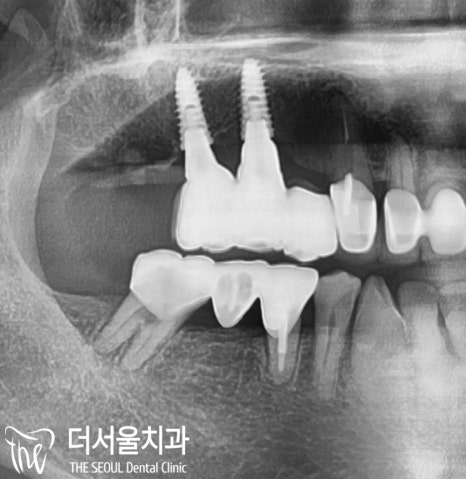

문제가 되는 아래 어금니를 살펴봅니다.

상태가 좋지 않네요.

내부는 더 깊게 썩어있는 상태였고,

그 옆에 있는 35번 작은 어금니 역시

마찬가지로 좋지 않은 상태였습니다.

성남치과 는 재신경치료를 하더라도

예후가 좋지 않았기 때문에

두 번의 치료를 받는 것보다,

임플란트 수술을 통해

좀 더 편안한 날을 더 보내시는게

좋다는 판단을 내렸습니다.